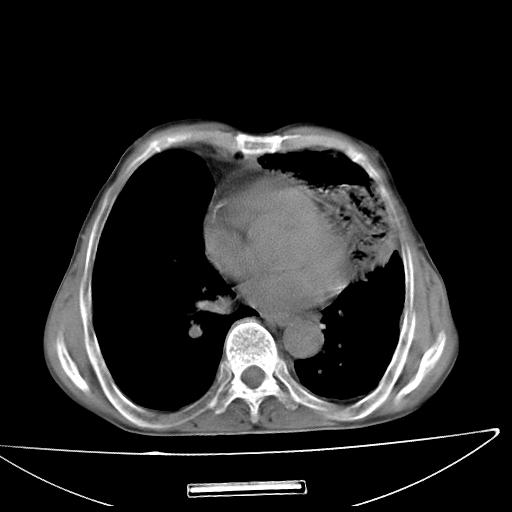

男  70岁,发烧咳嗽4天。盗汗,消瘦。无痰中带血丝,以前有肺tb病史,ct见,双肺tb,左侧胸廓塌陷,左胸膜肥厚粘连。纵隔移位,右侧胸腔积液,大家说说那个心影前左肺舌叶除了肺大炮还有炎症还是干酪性肺炎?有占位吗?我看纵隔淋巴结也大。

1)两肺继发性肺结核并左肺上叶肺不张,支气管扩张。2)双侧胸膜炎(胸膜增厚+少量胸腔积液)。

两肺继发性肺结核并感染,左肺上叶肺不张。建议ct增强。